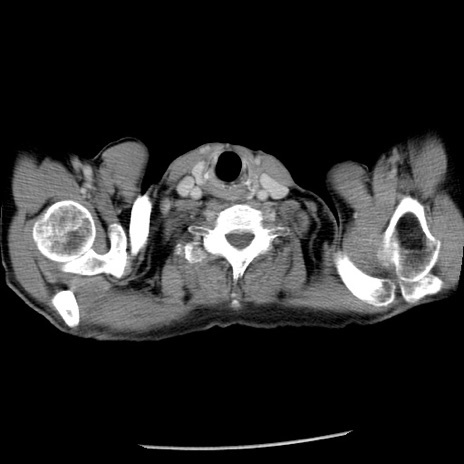

冠状断像